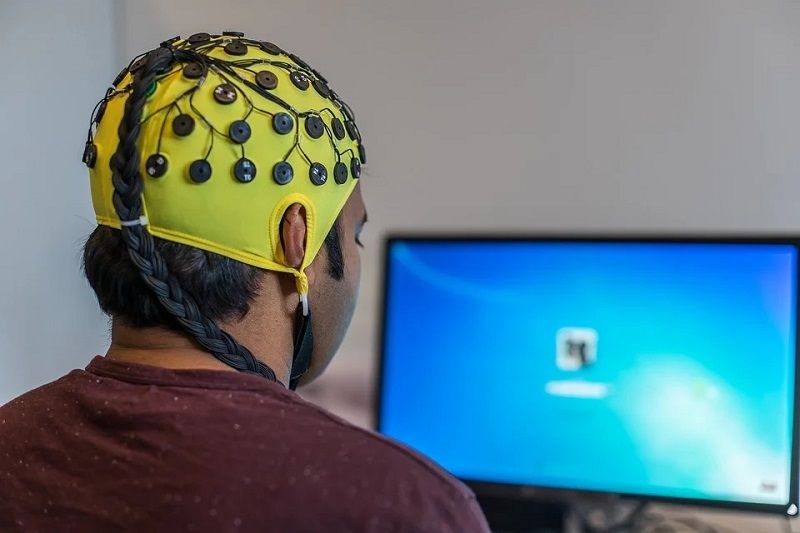

Az agyi aktivitást alvás közben követték, amikor a működés ingerfüggetlen, cselekvésirányítástól mentes aspektusai a leginkább megvalósulnak.

Egy gerincvelő-sérülés miatt nyaktól lefelé majd egy évtizede lebénult ember gondolatait használta fel arra, hogy valós idejű mondatokat alkosson – adta hírül a CNN amerikai hírtelevízió honlapja. A kaliforniai Stanford Egyetem kutatói két pici – 4-szer 4 milliméteres elektródákból álló – szenzort ültettek a férfi agyának bal féltekéjébe, képessé téve őt arra, hogy leírja gondolatait…